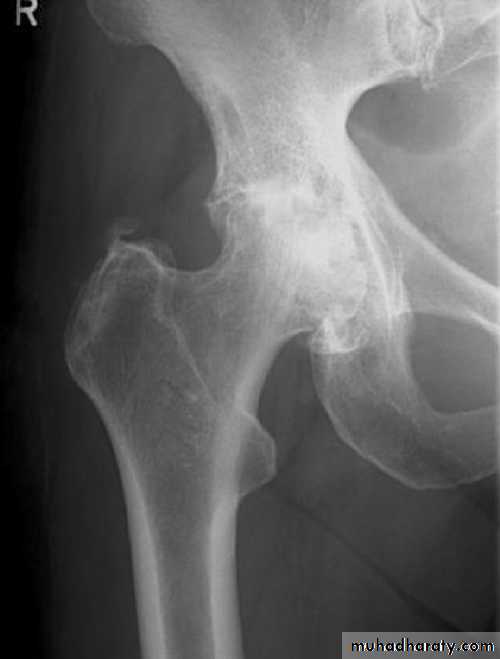

1- avascular necrosis of the femoral head ,appear in the x-ray as an increase in density of the femoral head , but it is not seen before 6 weeks and some time up to 2 years .In early weeks , bone scan and MRI will be helpful in the diagnosis of ischemia .

1- a vascular necrosis of the femoral head .

Early diagnosis by MRI

few weeks later we can diagnose it by bone scan .

X-ray changes may not show itself for months or even years.

3- osteoarthritis of the hip joint .

Avascular necrosis of the femoral head will lead to osteoarthritis later on .The treatment is by total hip replacement .